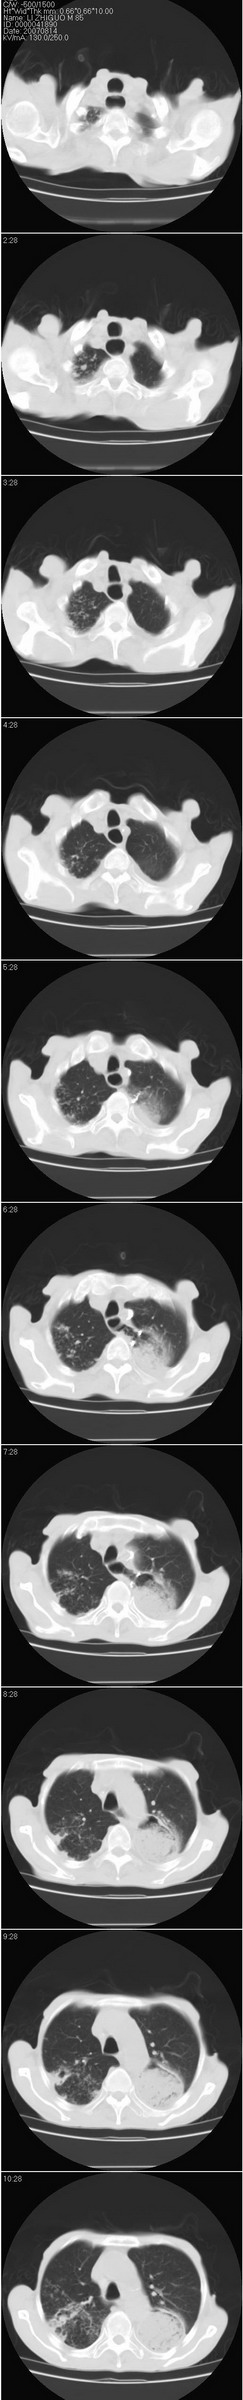

以下是引用dyqct在2007-8-18 14:40:00的发言:[br]考虑:1、食道弓上吻合术后(左侧胸腔胃);[br] 2、右上继发型肺结核;[br] 3、慢性支气管炎合并全小叶型肺气肿、感染。

以下是引用andymaomao在2007-8-18 14:29:00的发言:[br][br]1.该患者应有食道ca手术史,胃位于左侧胸腔(后纵膈旁);[br]2.双肺继发性肺tb?!不排除部分病灶改变为转移灶;[br]3.纵隔气管旁可见肿大淋巴结;[br]4.右下侧后胸壁轻度增厚、粘连。[br]5.另左肺部分肺组织含气不良(受压!?)。[br][br]